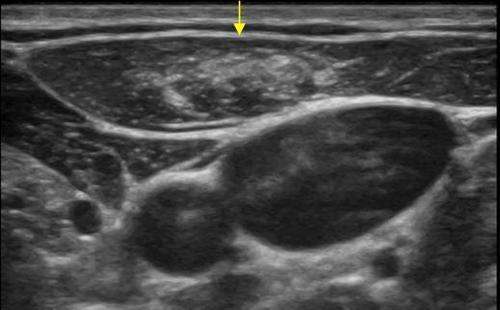

Bu inceleme ile cilt ve cilt altı dokudaki yağ bezeleri, yağ kistleri, yağ ve kıl kökü enfeksiyonları, yüzeyel yerleşimli varisler, varisler içerisinde olaşabilecek tıkanıklıklar, abseler, kas yapılar içerisindeki kitleler, kas yırtıkları ve kas içerisindeki kanamalar saptanabilir. Vücudumuzdaki bütün kas tendonu yapılarını bu yöntemle değerlendirebiliriz. Tendon hasarları, tendon kapsülünde sıvı artışı, ganglion kisti gibi sıklıkla görebildiğimiz tendon komşuluklarındaki kistler ve tendon kılıfından köken alan tümörler saptanabilir.